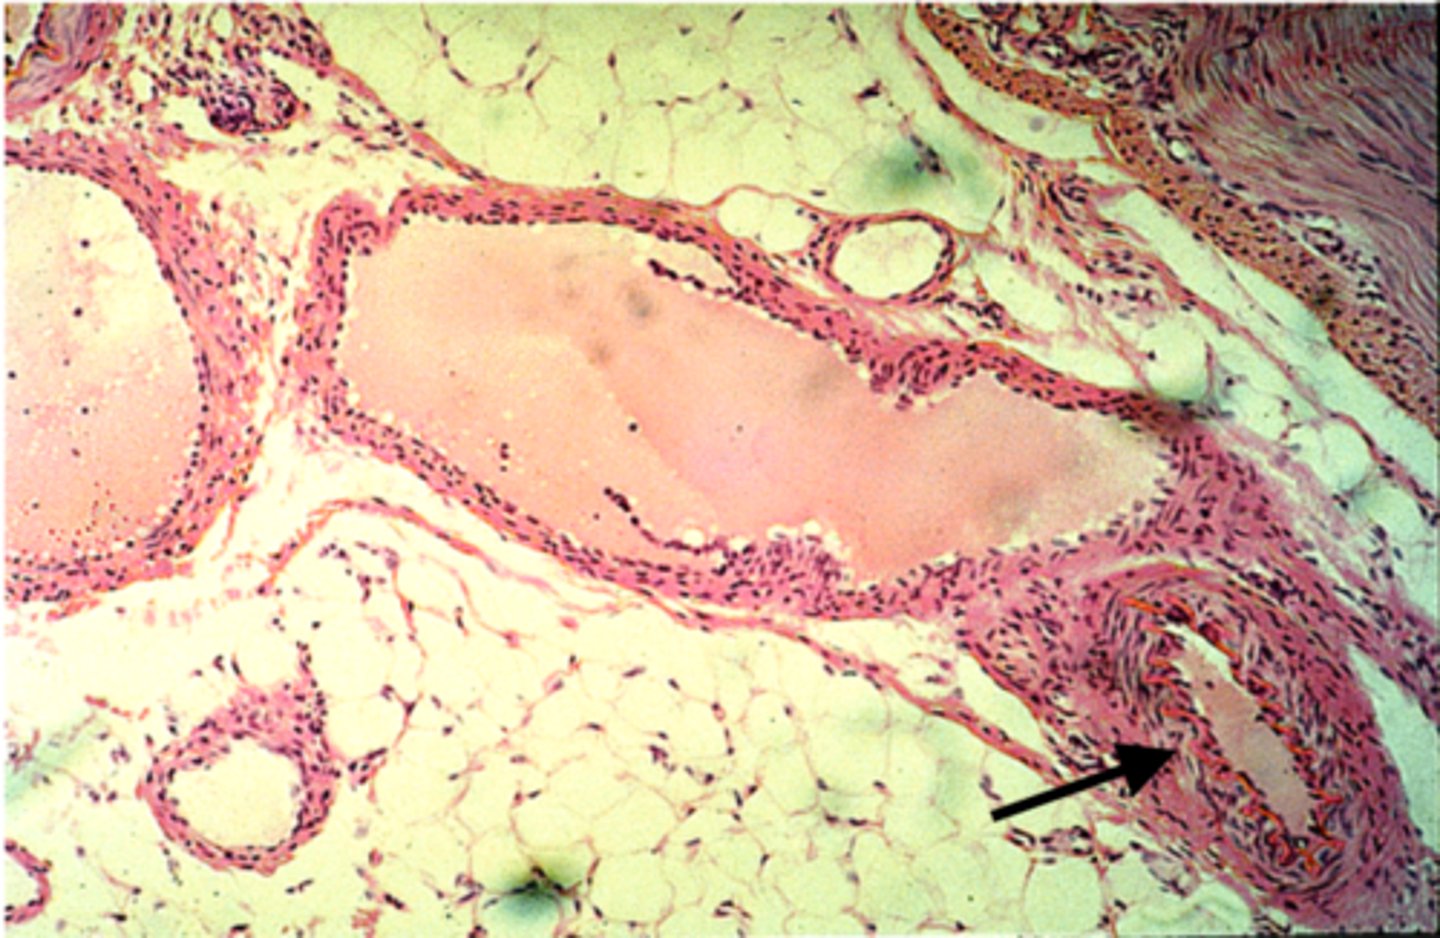

artery

what is this?

vein

what is this?

thicker inner wall

How to identify an artery

thinner inner wall

How to identify a vein